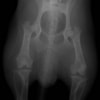

術前正面像

左後肢の挙上を主訴に来院されました。触診にて両関節の前方引き出し兆候、両膝蓋骨の内方脱臼を認めました。関節液検査より免疫介在性多発性関節炎は否定的でした。レントゲン検査にてfat pad signを伴う関節炎が認められたことから、前十字靭帯断裂と膝蓋骨内方脱臼(左GradeⅢ 右GradeⅢ〜IV)併発と診断し、手術を行いました。

術前のTPAは左後肢33.1°右後肢26.8°でしたがTPLO実施により左後肢5.5°右後肢12°に矯正されました。